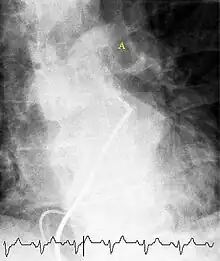

(A) After inhalation of 20 mCi of Xenon-133 gas, scintigraphic images were obtained in the posterior projection, showing uniform ventilation to lungs.

(B) After intravenous injection of 4 mCi of Technetium-99m-labeled albumin, scintigraphic images shown here in the posterior projection. This and other views showed decreased activity in multiple regions.

A ventilation/perfusion scan (or V/Q scan or lung scintigraphy) shows that some areas of the lung are being ventilated but not perfused with blood (due to obstruction by a clot).[18] This type of examination is as accurate as multislice CT, but is less used, due to the greater availability of CT technology. It is particularly useful in people who have an allergy to iodinated contrast, impaired kidney function, or are pregnant (due to its lower radiation exposure as compared to CT).[63][64][65] The test can be performed with planar two-dimensional imaging, or single photon emission computed tomography (SPECT) which enables three-dimensional imaging.[56] Hybrid devices combining SPECT and CT (SPECT/CT) further enable anatomic characterization of any abnormality.[66]